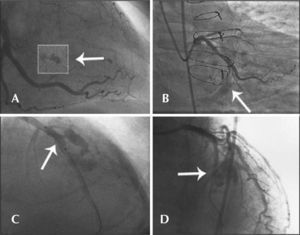

Type I: extraluminal crater with no linear contrast extravasation that suggests dissection (Figure 1A);

Figure 1.– In A, the left circumflex artery with an extraluminal crater (type I Ellis perforation). In B, the left circumflex artery with contrast extravasation into the pericardium with an orifice<1mm diameter (type II Ellis perforation). In C, left anterior descending artery showing rupture in its middle third, with diameter>1mm and significant extravasation of contrast outside the arterial lumen (type III Ellis perforation). In D, rupture of an important septal branch (left anterior descending artery branch) showing extravasation of contrast to the septum, with no extravasation of contrast to the pericardium (type IV Ellis perforation).

Type II: myocardial or pericardial blushing with an orifice<1mm (Figure 1B);

Type III: frank contrast medium extravasation into the pericardium through an orifice>1mm in diameter (Figure 1C) and

Type IV: perforation with contrast extravasation directly into the left ventricle, to the coronary sinus or other vascular chamber, excluding the pericardium (Figure 1D).

Simple perforations (type I) occurred in 33.3% (6/18) of patients, and their management included expectant and/or conservative treatment in four of six cases. Type II coronary perforations (27.8%, 5/18) were associated with guidewires (n=2) or balloon-catheter dilation (n=3). In these cases, the treatment included the administration of protamine for heparin inactivation associated with prolonged balloon inflation, and there was in-hospital periprocedural AMI in two cases. The type III coronary perforations were more often associated with ruptures caused by balloon catheters (50%), and one case had cardiac tamponade, requiring emergency surgery. Figure 2 shows the case with pericardial extravasation treated by prolonged inflation. Type IV perforation occurred in one patient post-dilation. There were no deaths associated with coronary perforation in any of the 18 cases, and the success rate of the procedure was 77.8% (n=14), as there was failed attempted occlusion recanalisation in three cases and suboptimal angiographic results (residual stenosis>30%) in one case. The median length of hospitalisation was 3.1days (range 2-58 days), and one patient who underwent emergency surgery presented a number of postoperative complications, including renal failure, requiring hemodialysis.

– In A, arterial lumen rupture with diameter>1mm and contrast extravasation through an orifice (type III Ellis perforation). Note the position of the balloon catheter in place to achieve prolonged inflation. In B, the balloon catheter inflated at the site of perforation and positioning of a pigtail catheter into the pericardial cavity after performing the pericardiocentesis.